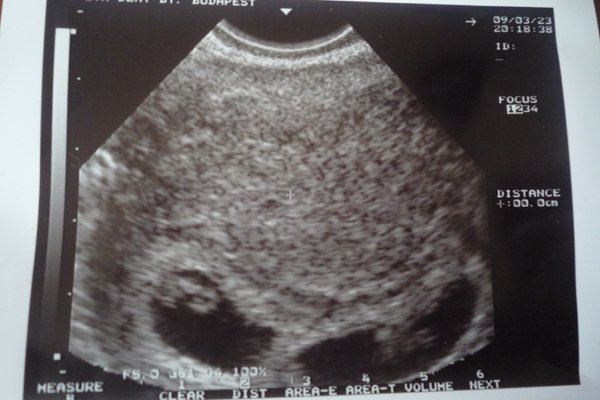

Jövő héten szerdán kell visszamennem UHU-ra, ha minden rendben lesz addig, márpedig miért ne lenne!